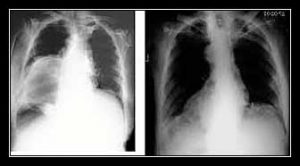

- Soi X-quang: nửa vòm nhô lên cao và bất động;

- Chụp X-quang: nửa vòm nhô lên cao.